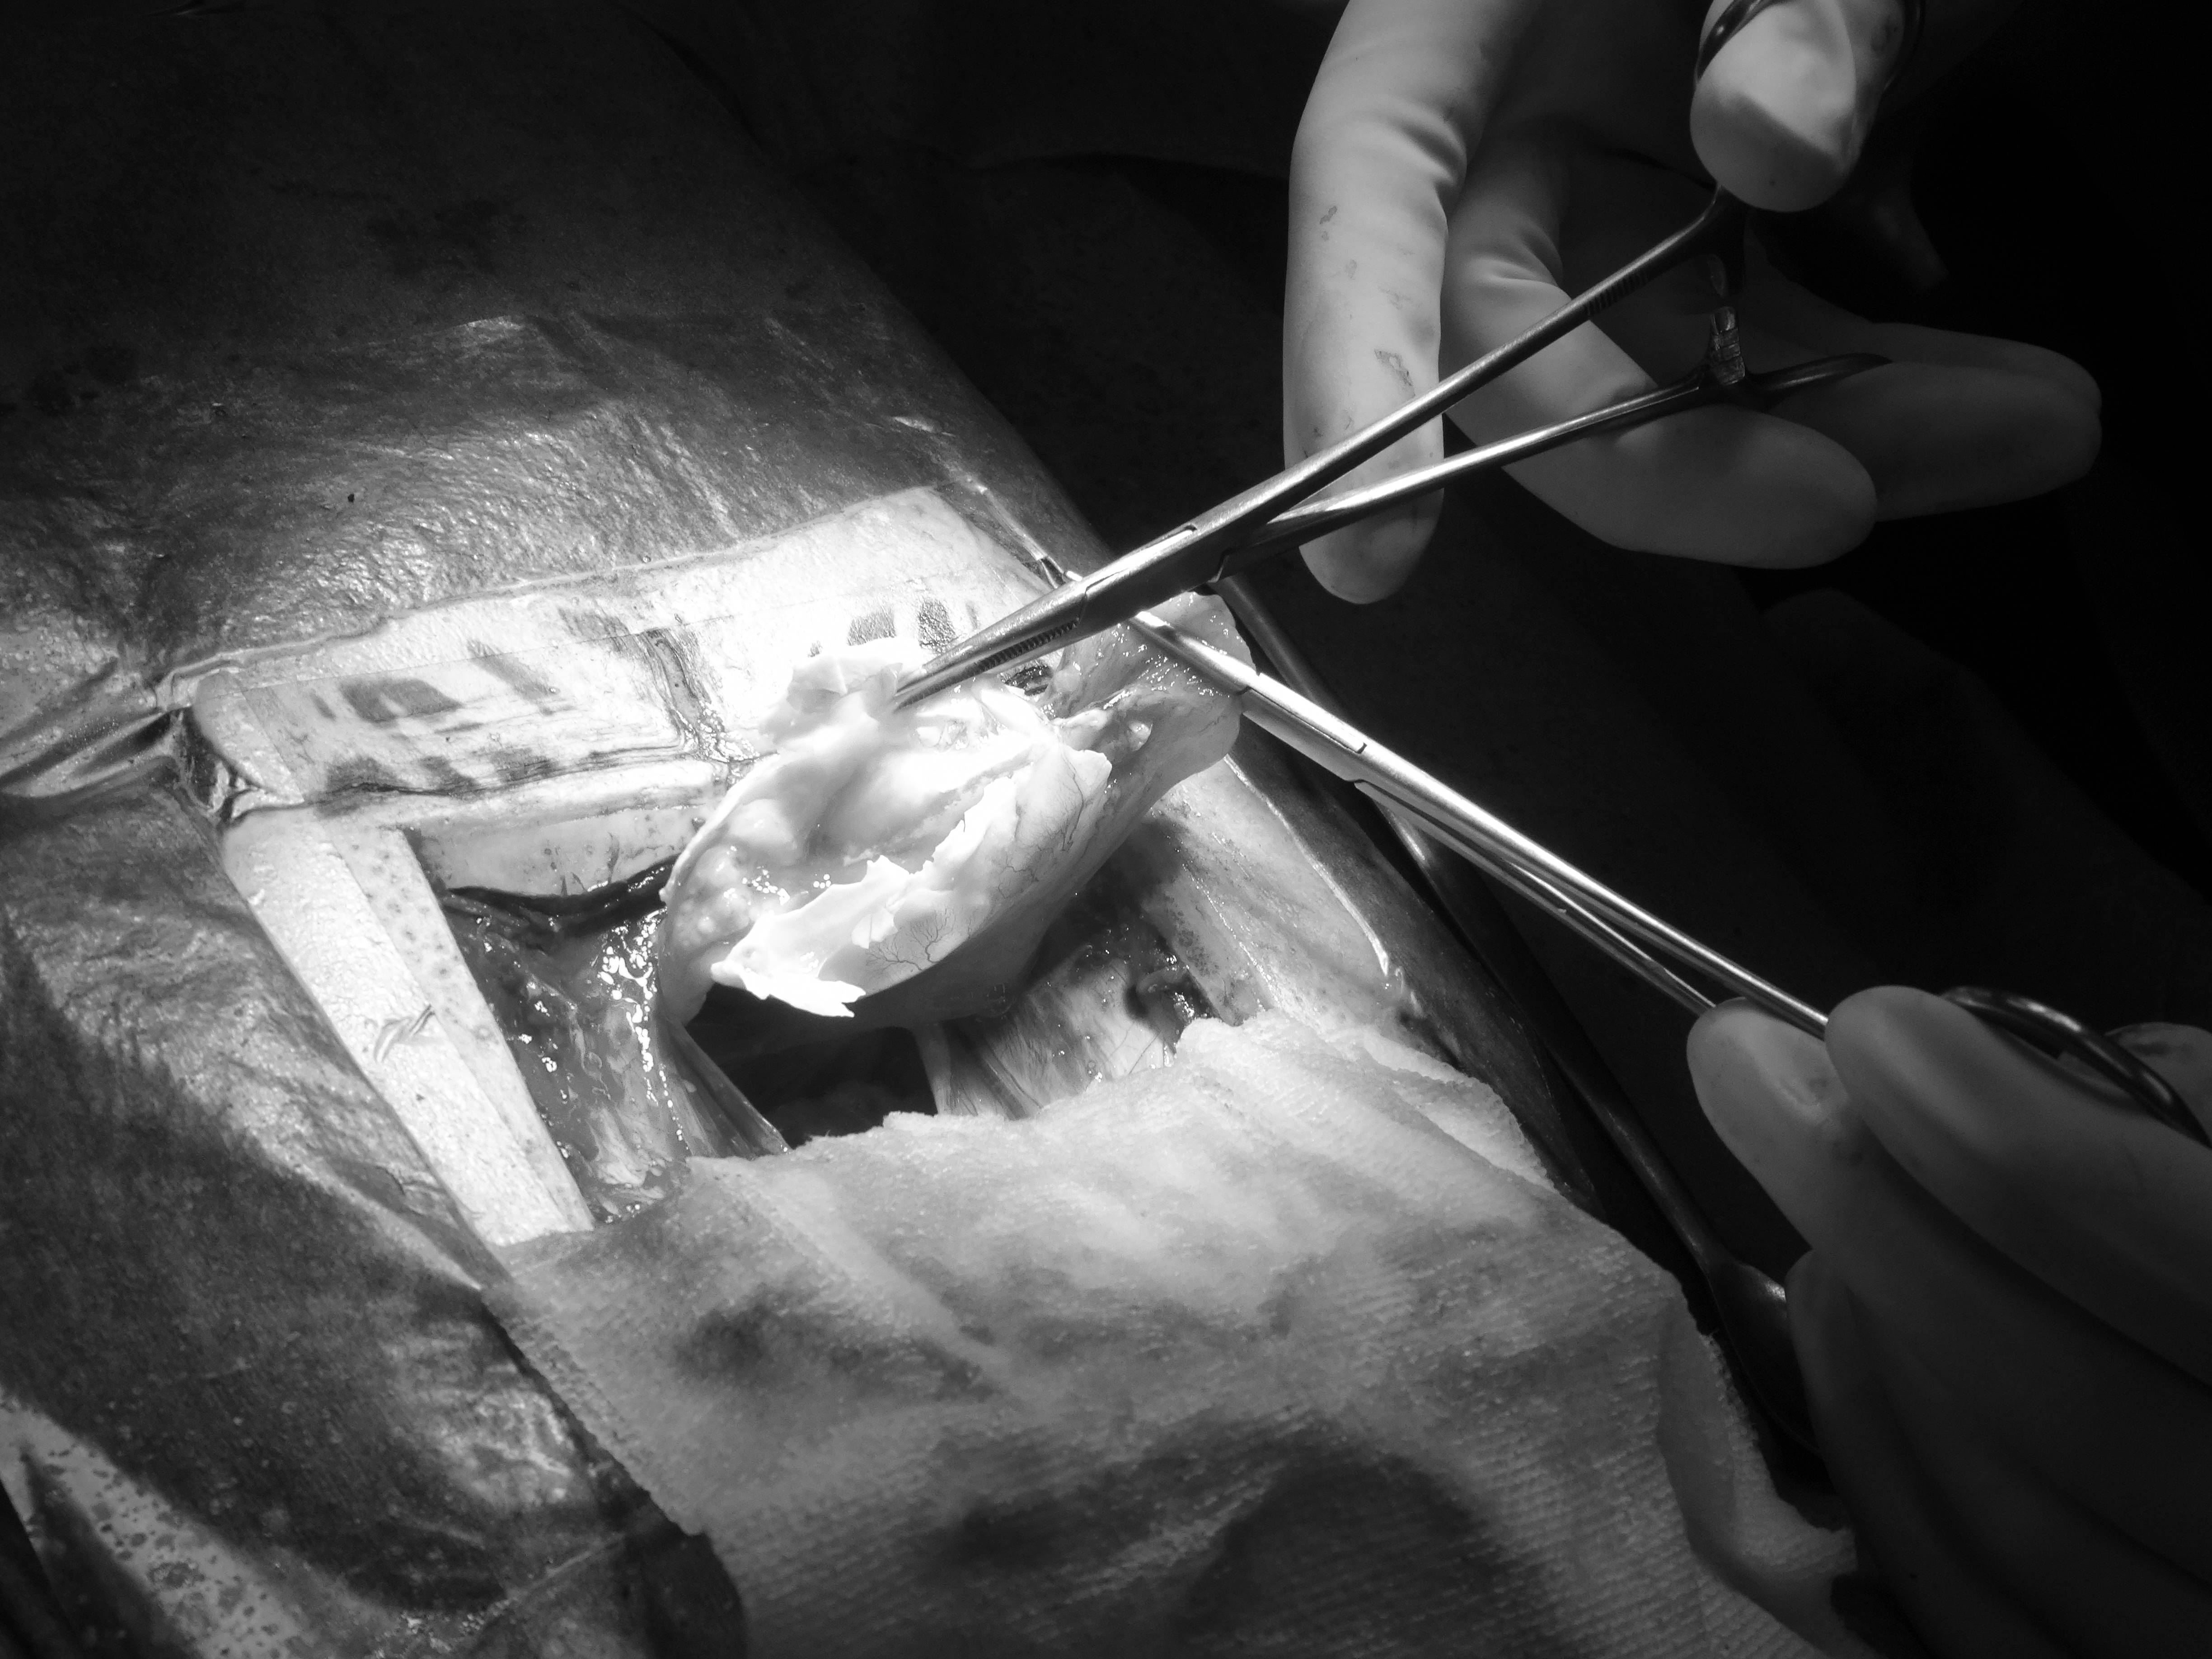

そのあとは哺乳類や鳥類と同じように、腹膜を切開して、卵巣と卵管を切除しました。

なかなか産まれなかった卵は、卵管の外にある状態(卵墜といいます)だったので、取り出しました。

一部は膀胱にくっついていたので、その部分の膀胱を切除し縫合しました。

すべて終わると腹膜を元通り閉じて縫合し、甲羅も閉じます。